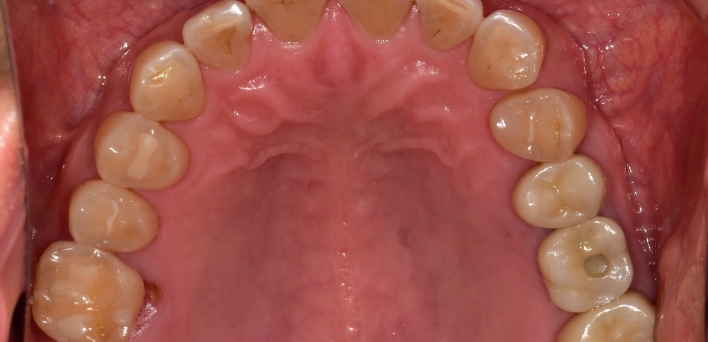

임플란트 : 손 ** 님 (50대)

치아가 있다는게, 아직도 정말 꿈만 같아요.

Before Before

2020.02.30

After After

※ 더서울치과의원은 의료법을 준수하며 위 케이스는 실제 환자의 동의를 얻은 사례로 치료 전, 후가 동일한 환경에서 촬영되었습니다.

환자 케이스에 따라 부작용이 발생할 수 있습니다. 이 부분은 의료진의 충분한 상담과 체크를 통해 예방하고 줄일 수 있습니다.

[임플란트 부작용] 수술 후 관리가 소홀할 경우 출혈, 주위염 등의 부작용이 발생할 수 있어 구강 위생을 철저히 유지하고, 정기적인 검진을 통해 상태를 점검하는 것이 중요합니다.

환자 특징

환자 특징01무치악 상태

환자 특징02수년간 무치악으로 지내심

임플란트가 불가능할것이라

생각하고 내원

위, 아래 6개씩 식립

디지털 풀아치 임플란트

임플란트 케이스

임플란트 Before & After